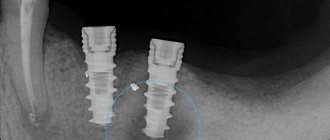

Выбор размера имплантата происходит после измерения диаметра корня на разных уровнях. Критерии выбора имплантата (см. фото 12):

• длина имплантата должны быть на 2-5 мм больше лунки;

• ширина — на 1-2 мм больше лунки.